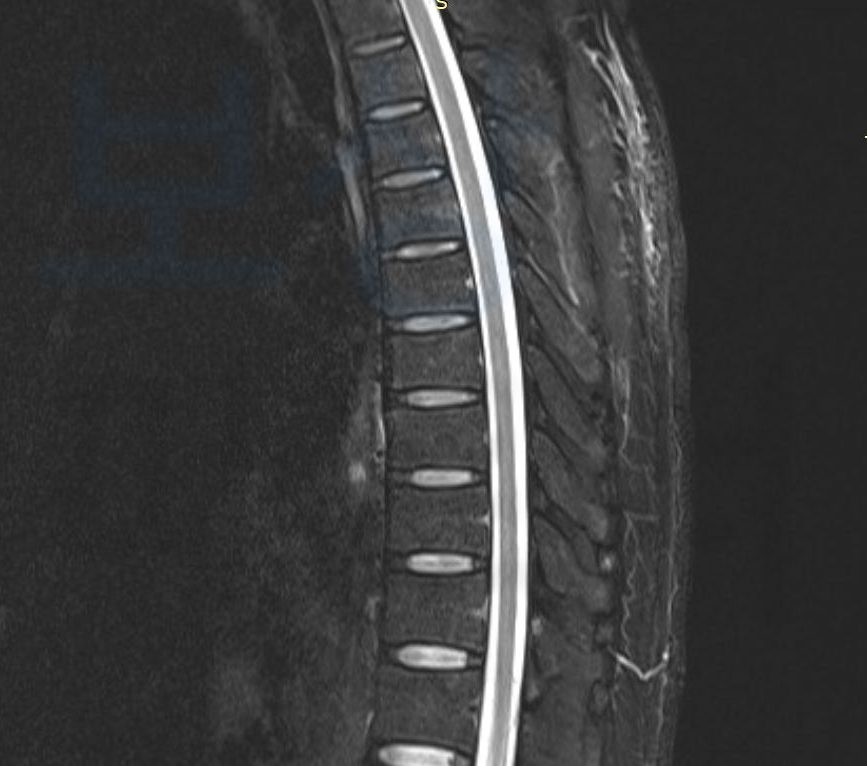

이때 일반 보험 소비자는 보험사에 대응할 경험이나 정보가 없기 때문에 속수무책으로 당할 수밖에 없는 입장이죠. 보상 파트너가 처리했던 보상 사례 소개해드리겠습니다. 현장에서 일하던 중 무거운 물체가 등뼈에 떨어지는 사고를 당한 고@@님, 극심한 통증을 호소하며 Mri 촬영 등의 정밀 검사를 시행하셨는데요, 검사 결과 고@@님은

image

S22090 흉추골절, 폐쇄성 진단받으셨고 최소 10주간의 허리 보조기 착용하며 보존적 치료를 하셔야 했습니다. 고@@님은 내 보험에서 청구할 수 있는 실비, 입원비, 골절 진단비를 이미 보상받으셨고 주변 지인으로부터 소개받아 보상 파트너로 연락 주시게 되었습니다.